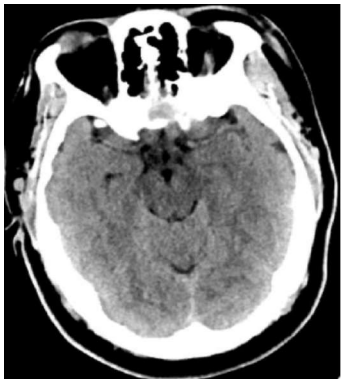

Uma mulher de quarenta anos de idade, obesa, hipertensa e tabagista, em uso irregular de hidroclorotiazida e anticoncepcional oral, compareceu ao pronto-socorro, queixando-se de cefaleia súbita de forte intensidade, iniciada há cerca de 12 h e associada a episódio de vômito. Refere que apresentou episódios semelhantes nas últimas duas semanas, de menor intensidade. Realizou a tomografia de crânio mostrada a seguir.

Enunciado 1994010-1

Internet: © 2017 Elliot K. Fishman, MD.

Com base nesse caso hipotético, assinale a alternativa que apresenta a conduta a ser adotada inicialmente.